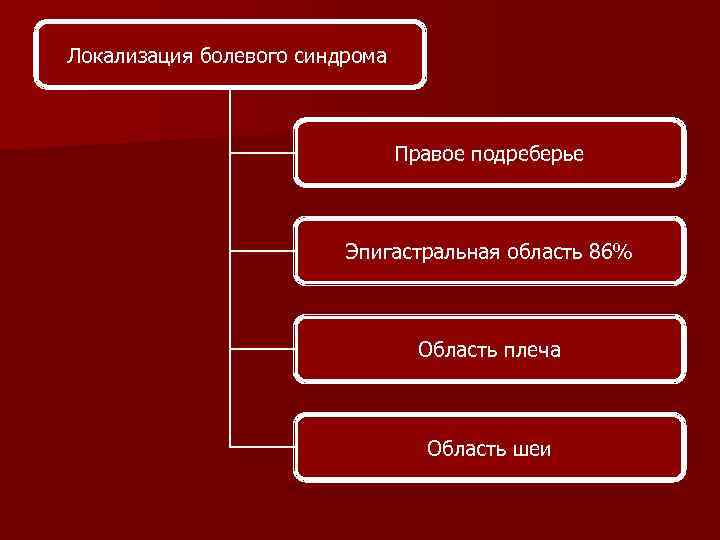

Диагностика Беременность Болевой синдром (86% эпигатральная локализация) Нарушения функции печени Тромбоцитопения

Диагностика Беременность Болевой синдром (86% эпигатральная локализация) Нарушения функции печени Тромбоцитопения

Локализация болевого синдрома Правое подреберье Эпигастральная область 86% Область плеча Область шеи

Локализация болевого синдрома Правое подреберье Эпигастральная область 86% Область плеча Область шеи